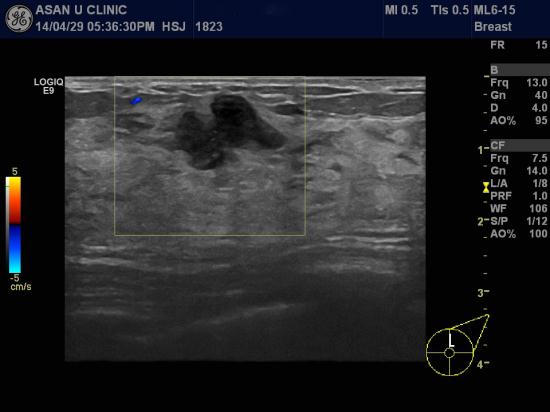

아산유외과 개원 후 96번째 유방암진단.

건강검진상 이상소견으로 내원한 43세 여성분입니다.

1.6cm의 좌측 유방의 침윤성 유관암으로 조직검사상 진단되었습니다.

혹이 피부 근처에 있어 진찰상 잘 만져졌으나

유방을 만져본적이 없다고 하시며 웃으십니다.